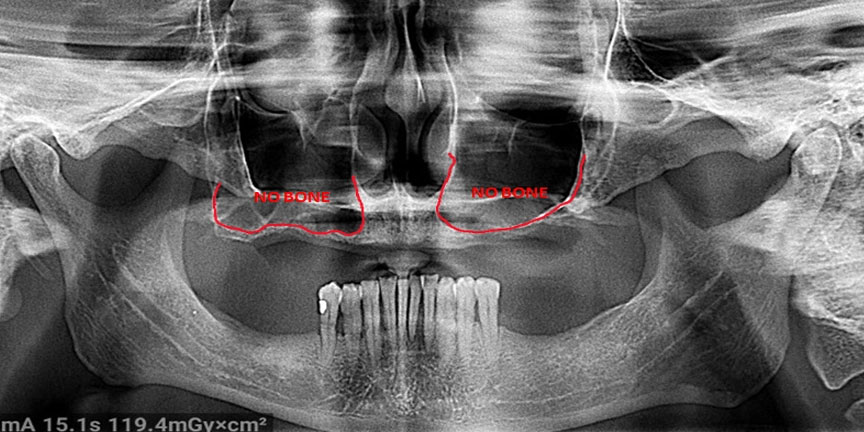

Difficult Cases

We treat patients when other providers cannot manage.

Severe Bone Loss